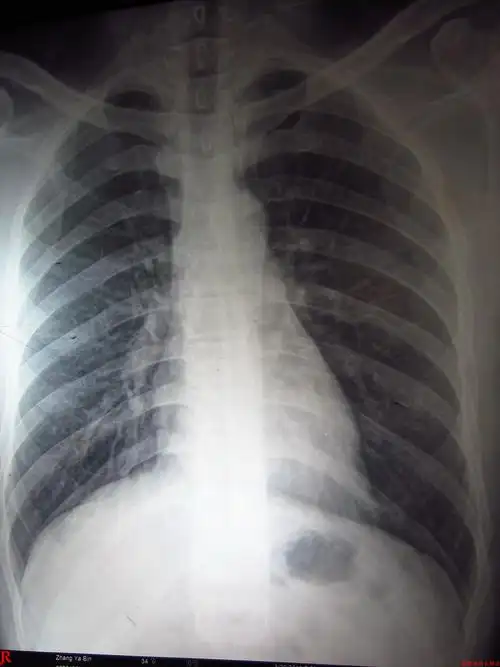

这张胸片肺部有问题吗?